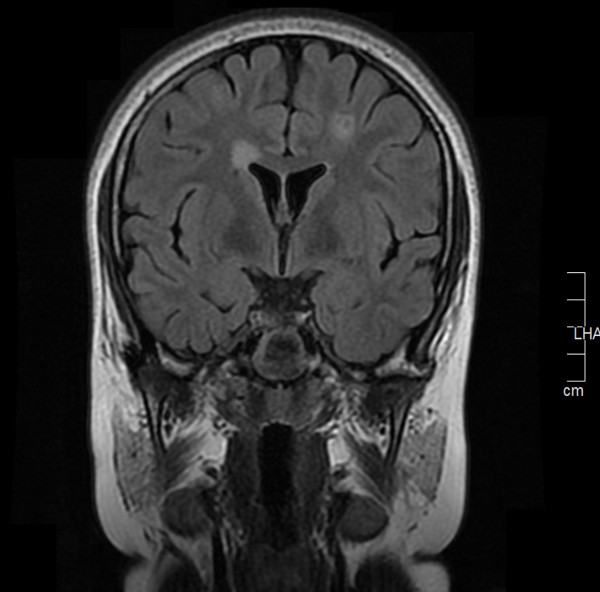

Se realiza una RM craneomedular. El estudio cerebral pone de manifiesto múltiples lesiones focales (aproximadamente 25, de entre 5 y 20 mm) predominantemente hiperintensas en secuencias T2. Afectan a la sustancia blanca yuxtasubcortical y periventricular de ambos hemisferios cerebrales, incluyendo el cuerpo calloso y el troncoencéfalo. Múltiples de las lesiones supratentoriales muestran una señal de resonancia heterogénea tanto en las secuencias T1 como T2, con un patrón interno en anillos concéntricos (patrón tipo Balo).

Se observa realce heterogéneo tras la administración de contraste en dos de las lesiones situadas en los hemisferios cerebrales, así como de la lesión que se sitúa en la hemiprotuberancia derecha afectando el trayecto intraparenquimatoso del nervio trigémino y comprometiendo también la emergencia del nervio facial derecho.